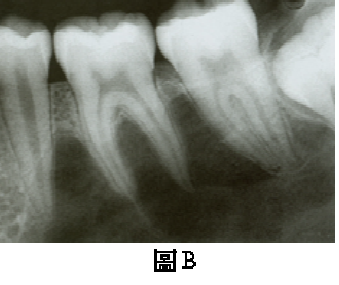

68. 下圖之下顎後牙區之根尖片影像,發現只有左下第一大臼齒有異常,最可能之臨床診斷為:

(A)牛牙(taurodontia) (B)先天性梅毒(congenital syphilis) (C)牙本質發育不全(dentinogenesis imperfecta) (D)牙釉質發育不全(amelogenesis imperfecta)